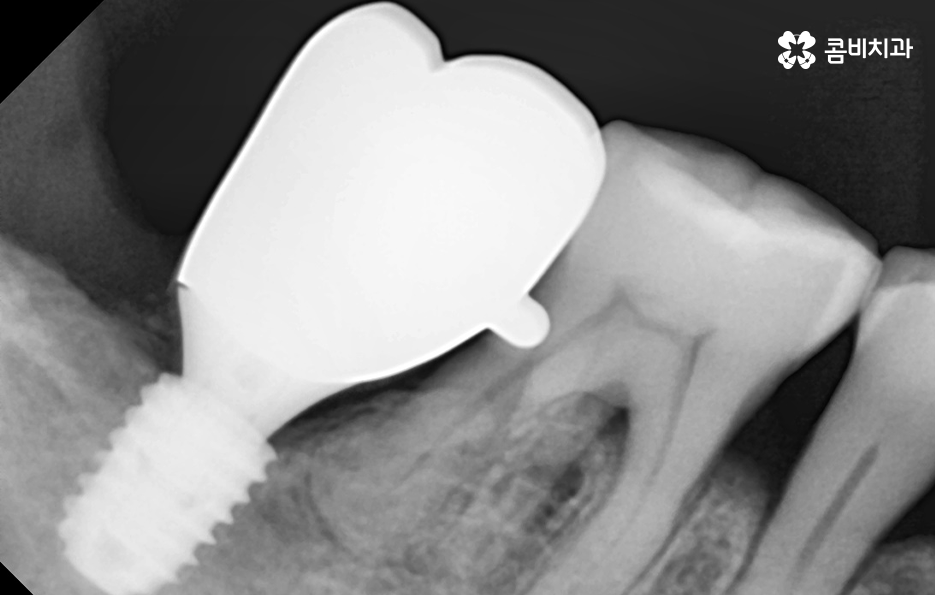

그 중에서도 치주염으로 인해 위에 보시는 사례 사진처럼 잇몸은 내려앉고 치아 뿌리가 외부에 상당 부분 드러나는 경우에는 우선 일상에서 치아가 무척이나 시리고 통증을 느끼게 되며 치주염이 결국 잇몸 뼈를 녹게 만들어서 치아 뿌리가 흔들리고 결국 발치하게 되는 경우가 많아요

임플란트의 시술 원리는 잇몸 뼈에 식립하게 되기 때문에 충분한 골조직이 없을 때는 시술 성공률도 낮아질 뿐 아니라 장기적인 안정성도 떨어지기 때문에 잇몸 뼈가 부족하신 분들은 뼈이식을 추가적으로 해야할 수 있어요

만약 치주염으로 인해 50대임플란트 해야 하는 분들의 경우에는 뼈이식을 추가적으로 받아야 하는 경우가 있겠고 임플란트의 안정성을 확보하기 위해서는 임플란트를 고정해줄 수 있는 일정한 두께와 식립 깊이, 골질이 건강해야 하는데요